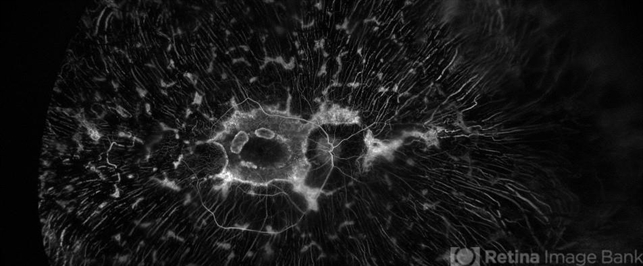

- retinitis pigmentosa

- Jeffrey P. Barker

- Scanning laser ophthalmoscope

- FA OD